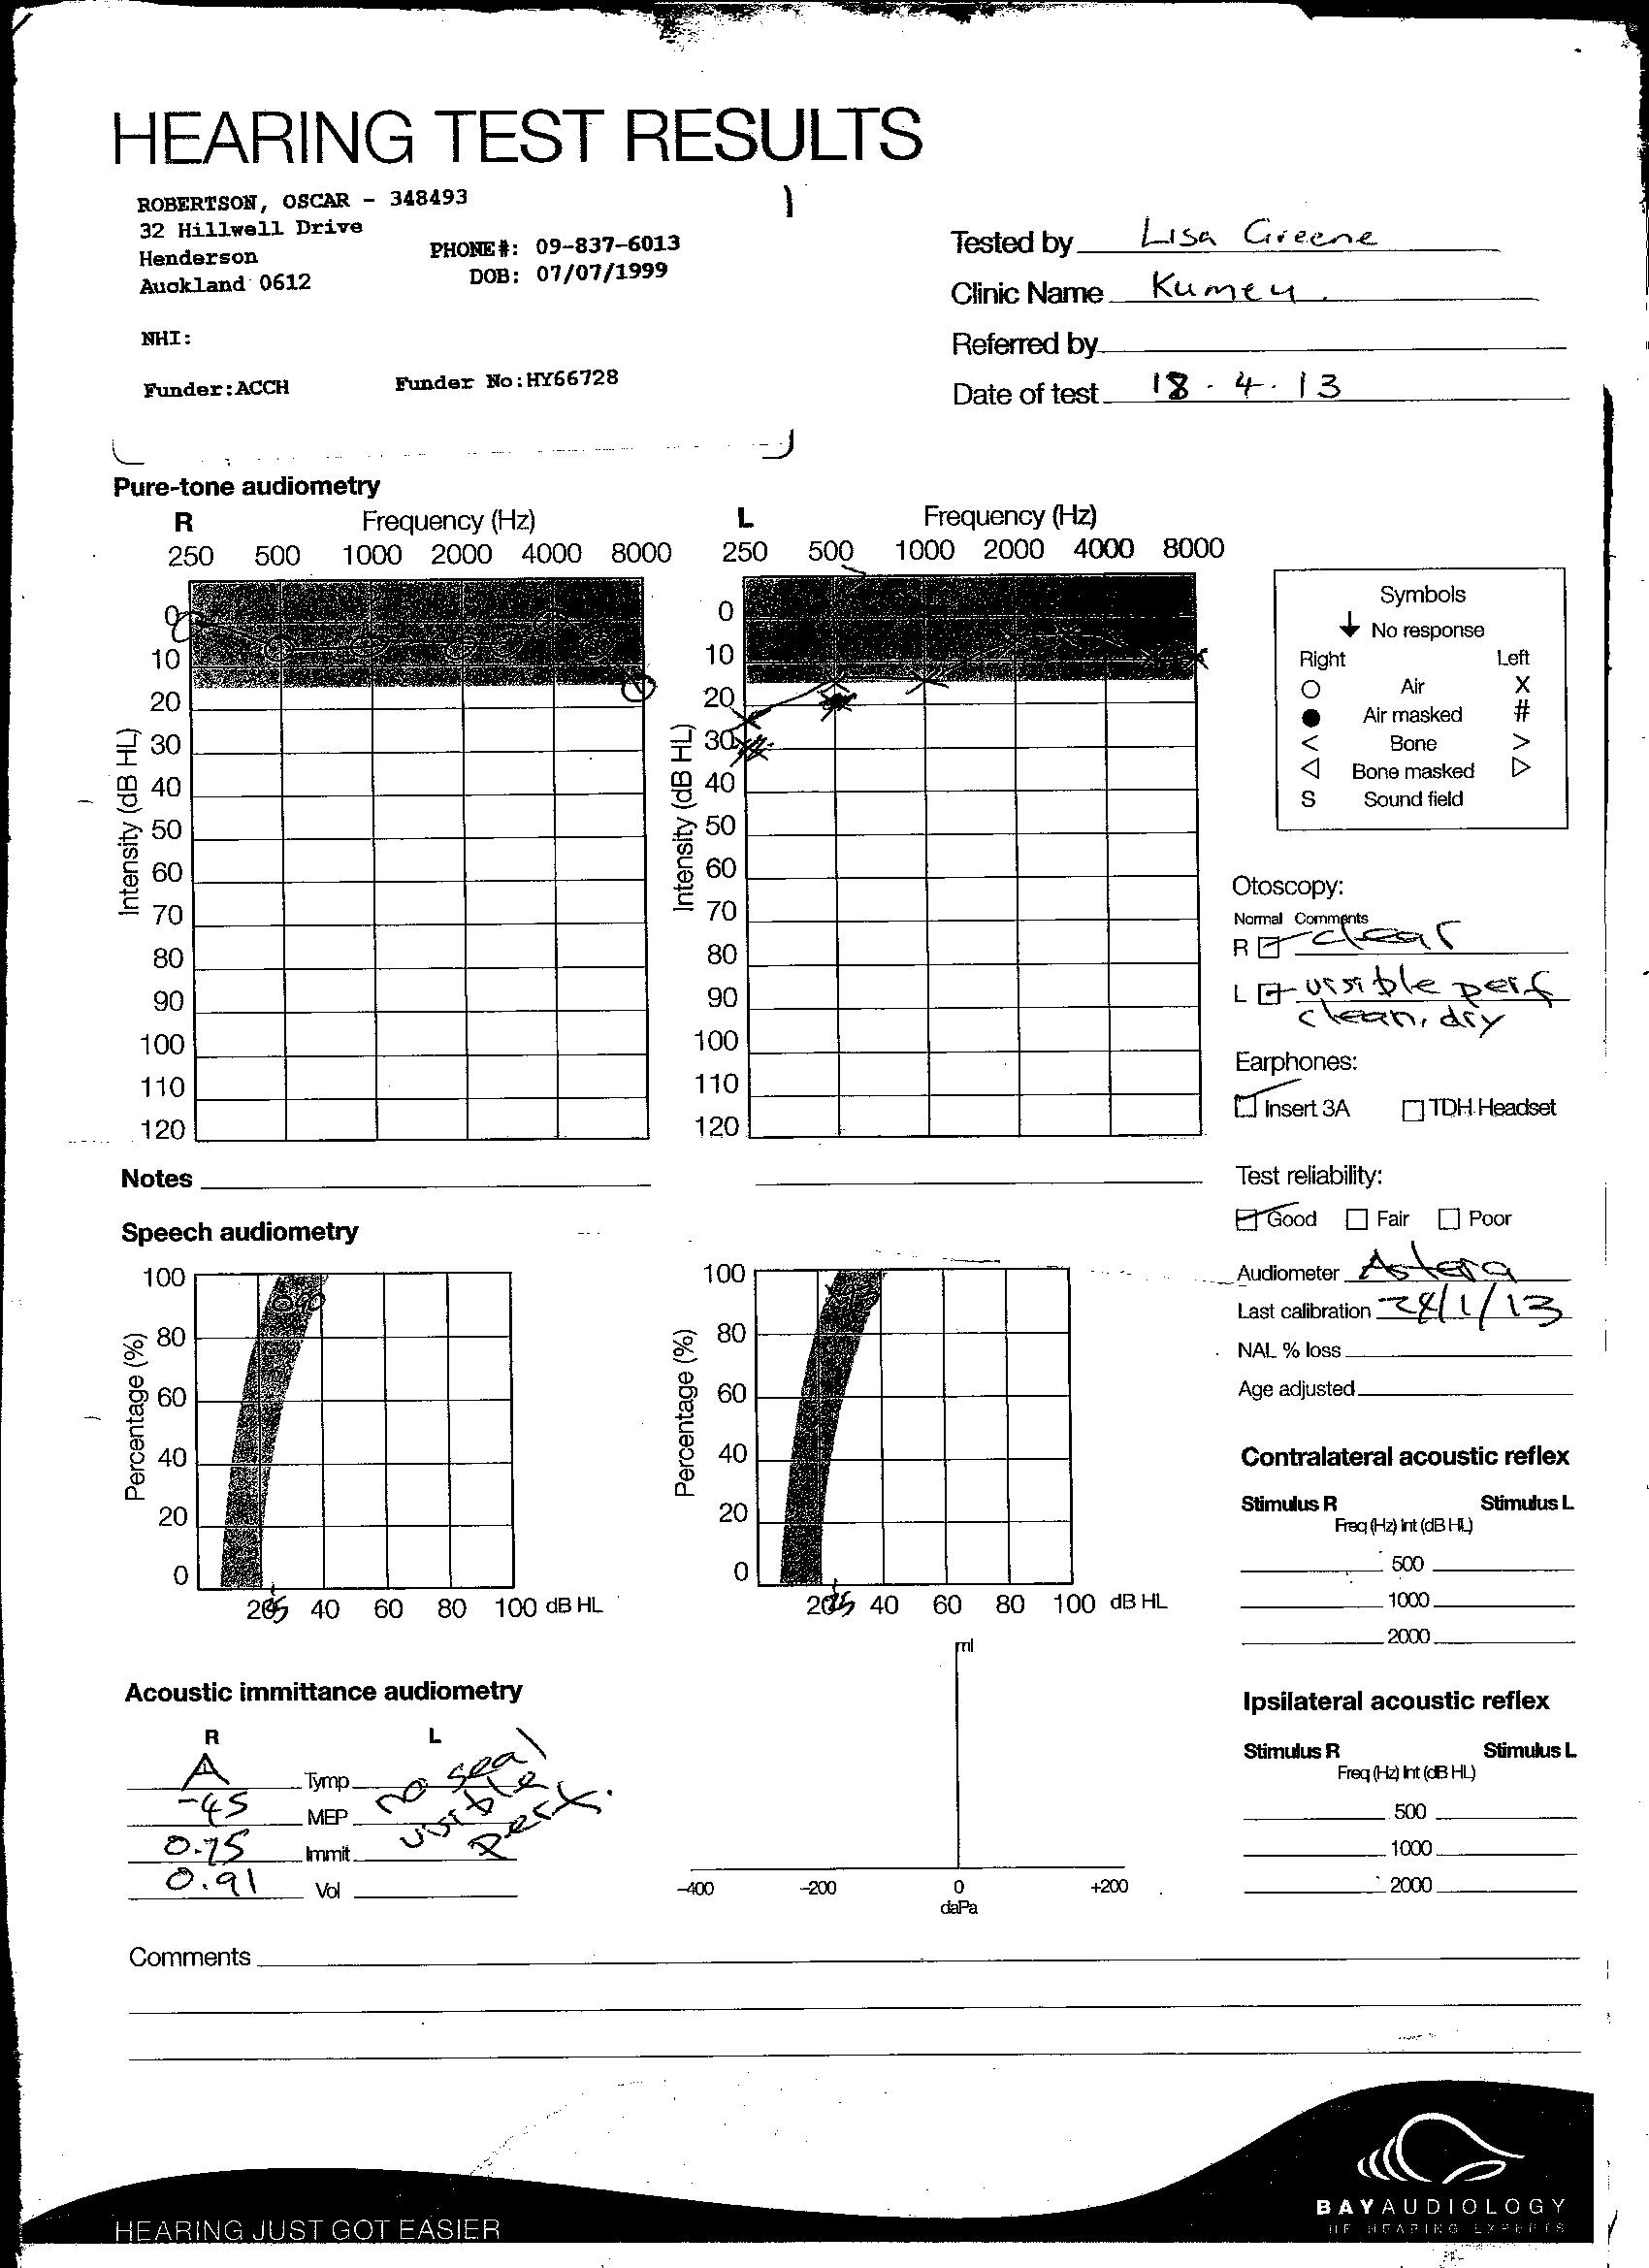

Medical Wrap, Moon Boot, House Paint, Car Mats, Wetsuit, Projection, Casts, Video Work Forensics investigates trauma both physical and mental and how the two might interact through objectivity.